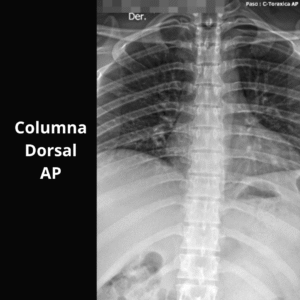

- Columna Dorsal O AP O LAT O OBL